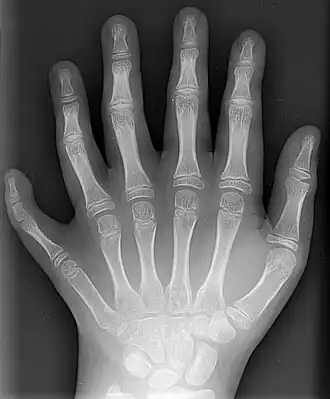

Un doigt est composé de trois phalanges, sauf le pouce et le gros orteil, qui n'en ont que deux[12]. Il s'agit, en partant de la paume, de la phalange, la phalangine[13] et de la phalangette[14].

Les jonctions entre les os du doigt sont nommées articulations interphalangiennes. Celles entre les doigts et la paume de la main sont nommées articulations métacarpo-phalangiennes.